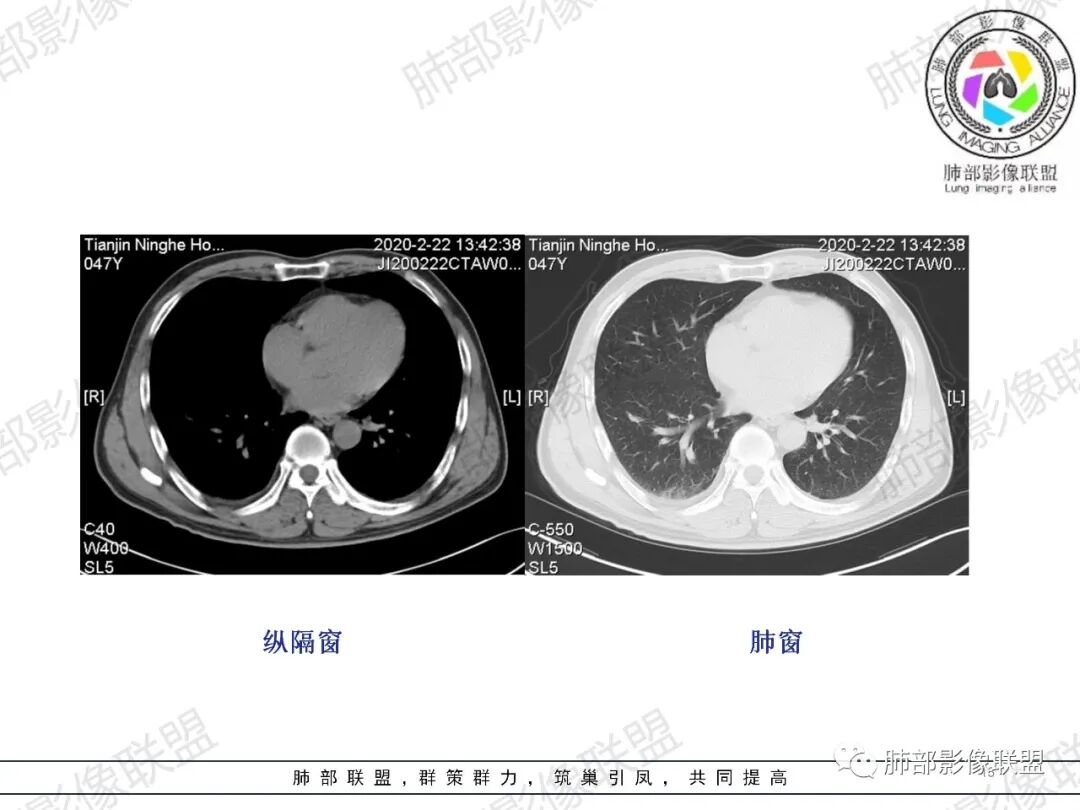

肺动脉栓塞

肺动脉栓塞(简称PE)为内源性或外源性栓子堵塞肺动脉或其分支引起肺循环障碍的临床和病理生理综合征,是常见的且具有潜在致死性的心血管疾病,90%为肺动脉血栓栓塞。

CT肺动脉成像(CTPA)以其高度的敏感度和特异度,已经作为临床上诊断急性肺栓塞的首选方法。

急性肺栓塞患者CTPA上胸部继发改变包括肺动脉干增粗、右心增大、肺梗死、马赛克征、Westermark征、心包积液、胸腔积液、肺不张/肺膨胀不良等。

肺动脉高压的标准以肺动脉干直径大于3 cm或肺动脉干直径大于同层面升主动脉直径。右心增大的标准以横断位四腔心层面右心室内径与左心室内径比值大于1,或出现室间隔变直或凹陷等征象。

急性肺栓塞发生后,因肺动脉血流阻断而引起供血动脉远端肺组织的坏死称为肺梗死。肺动脉分支一旦血流阻断,远端毛细血管网则因管壁缺氧而通透性增高,液体及红细胞随之渗出,肺泡腔内渗出物增加,必然会影响气体交换,随后肺梗死发生。既往有研究表明,肺外周楔形阴影可以认为是肺梗死的征象,是唯一与肺栓塞显著相关的肺实性异常,该征象在肺栓塞患者中的发生率为25%。

综上所述,中央型急性肺栓塞危险程度更高,更易引起肺动脉高压、右心功能不全、肺梗死及马赛克征等一系列的继发改变。早期确定栓塞类型对于对临床判断预后及选择治疗方式有一定的价值。